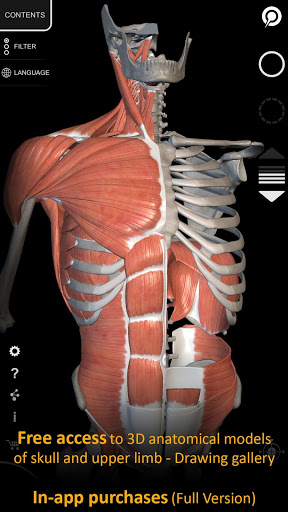

Ứng dụng này có thể tải xuống miễn phí, tuy nhiên cần phải mua trong ứng dụng để mở khóa nội dung.

Toàn bộ Hệ thống xương và một số nội dung khác luôn có thể truy cập miễn phí, cho phép bạn dùng thử ứng dụng một cách chính xác.

"Anatomy 3D Atlas" cho phép bạn nghiên cứu giải phẫu người theo cách dễ dàng và tương tác.

Thông qua giao diện đơn giản và trực quan, bạn có thể quan sát mọi cấu trúc giải phẫu từ mọi góc độ.

Các mô hình giải phẫu 3D đặc biệt chi tiết và có kết cấu lên đến độ phân giải 4k.

"Anatomy - 3D Atlas" là ứng dụng dành cho sinh viên y khoa, bác sĩ, chuyên gia vật lý trị liệu, nhân viên y tế, y tá, huấn luyện viên thể thao và bất kỳ ai quan tâm đến việc đào sâu kiến thức về giải phẫu người. Ứng dụng

này là một công cụ tuyệt vời để bổ sung cho các cuốn sách giải phẫu người kinh điển.

• Hình dung các cơ qua các lớp từ lớp nông đến lớp sâu nhất